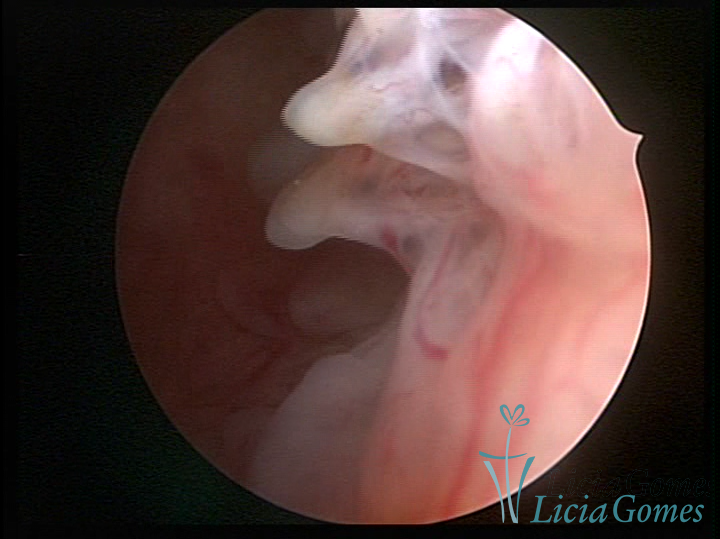

Este pode apresentar uma gama variável de aspectos macroscópicos, com aspecto pseudopolipoide; lembrando tecido cerebroide ou com reação deciduoide;a vascularização superficial é mais evidente e com vasos em formatos de saca-rolha ou espirais visualizando também a vascularização com atípias, com aumento do calibre dos vasos superficiais, pode ser encontrado também tecido em necrose, poderá haver um pequenos dendritos (papilomatoso).